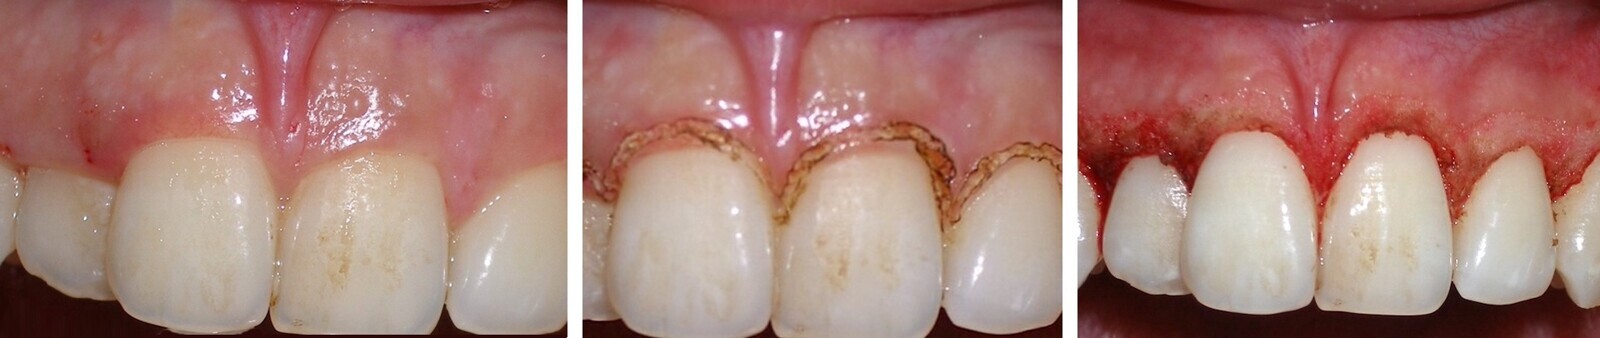

El tratamiento de estas pigmentaciones con el láser de diodo obtiene buenos resultados a nivel estético, es cómodo para el paciente durante y después de la intervención, y los resultados son muy estables a lo largo del tiempo (Figuras 6-8).

El láser de diodo obtiene buenos resultados estéticos en el tratamiento de pigmentaciones (ver Figuras 6-8).

Figura 6.

Figura 7.

Figura 8. Las figuras 6-8 muestran el tratamiento de las pigmentaciones con el láser de diodo obtiene buenos resultados a nivel estético y es cómodo para el paciente.